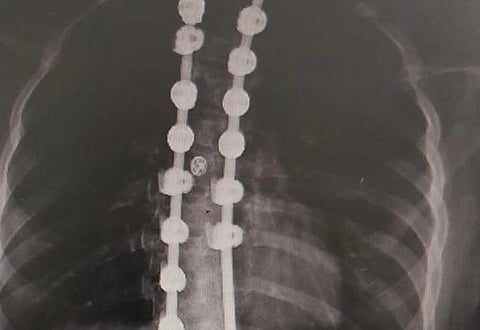

نجح - بفضل الله - فريق طبي متخصص في قسم جراحة عظام الأطفال بمستشفى أبها للولادة والأطفال، بقيادة رئيس القسم الدكتور مهدي القرني، في إجراء عمليتَيْ تقويم وتثبيت انحراف وتشوُّه العمود الفقري لطفلتَيْن، كانتا تعانيان آلامًا وتشوهًا وزيادة زاوية الانحراف للعمود الفقري الذي وصل لقرابة ١٠٠درجة.

كما تعتبر مثل هذه العمليات من الإجراءات الجراحية المعقدة والمتقدمة، التي تستخدم فيها أدوات جراحية متقدمة.